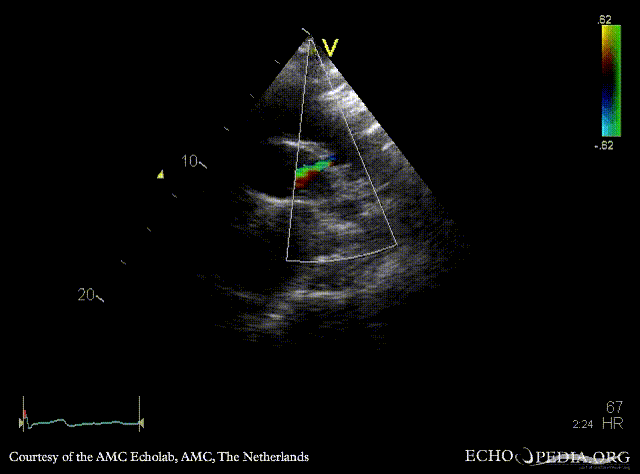

Open ductus Botalli

Suprasternal view with Color Doppler, open ductus Botalli, zoom